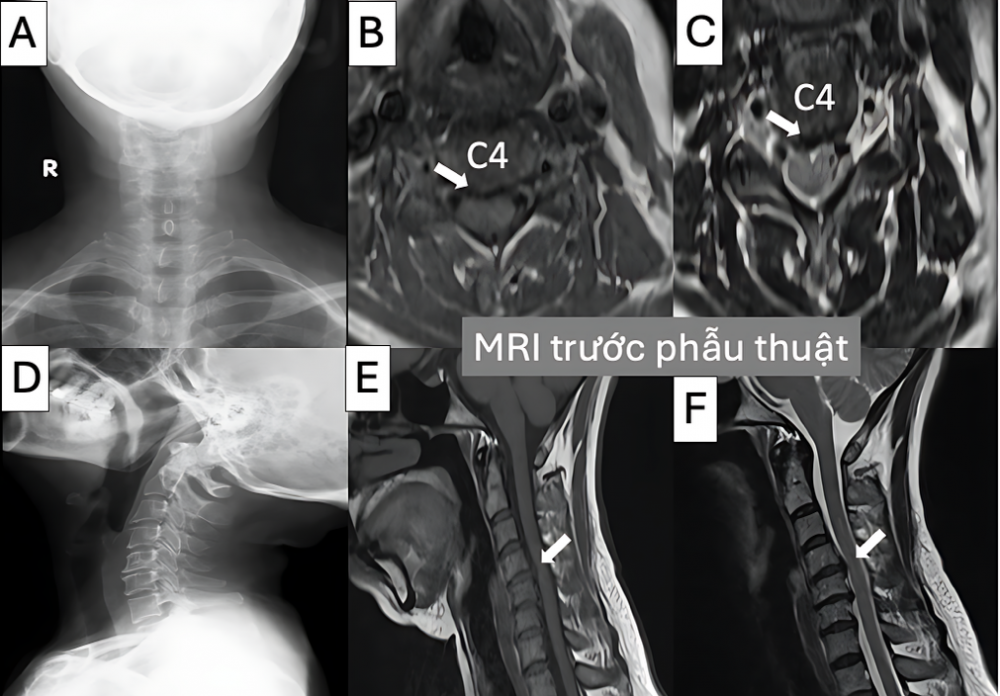

Hình 2. Hình ảnh trước mổ với phim X-quang cột sống cổ thẳng (A), nghiêng (D) và cộng hưởng từ chuỗi xung T1 (B, E) và T2 (C, F) trên hai mặt phẳng axial và sagittal cho thấy khối thoát vị đĩa đệm cổ C4-C5 đè ép vào tuỷ sống cố (mũi tên trắng)

Bệnh nhân nữ, 56 tuổi, vào viện vì đau cổ kéo dài lan xuống tay phải, tê bàn tay và yếu khi cầm nắm.

Chụp MRI cột sống cổ cho thấy thoát vị đĩa đệm C4–C5 chèn ép rễ thần kinh phải.